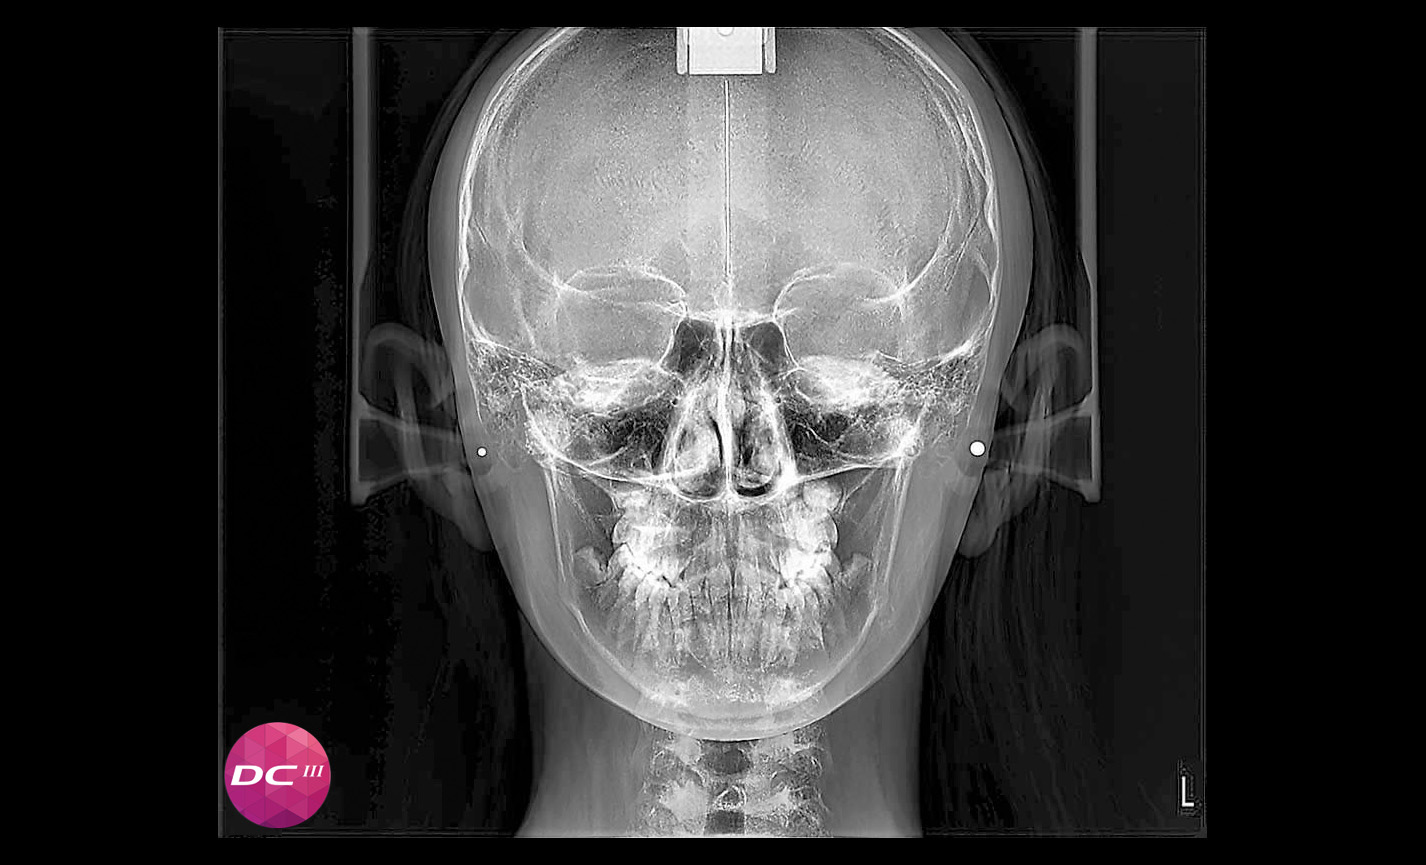

Projections antéro-postérieures et postéro-antérieures

Projections menton-vertex, y compris les incidences de Waters et de Towne renversées

Téléradiographie

Antéro-postérieure : pour investiguer les asymétries et les malocclusions en vue d’un traitement correct.